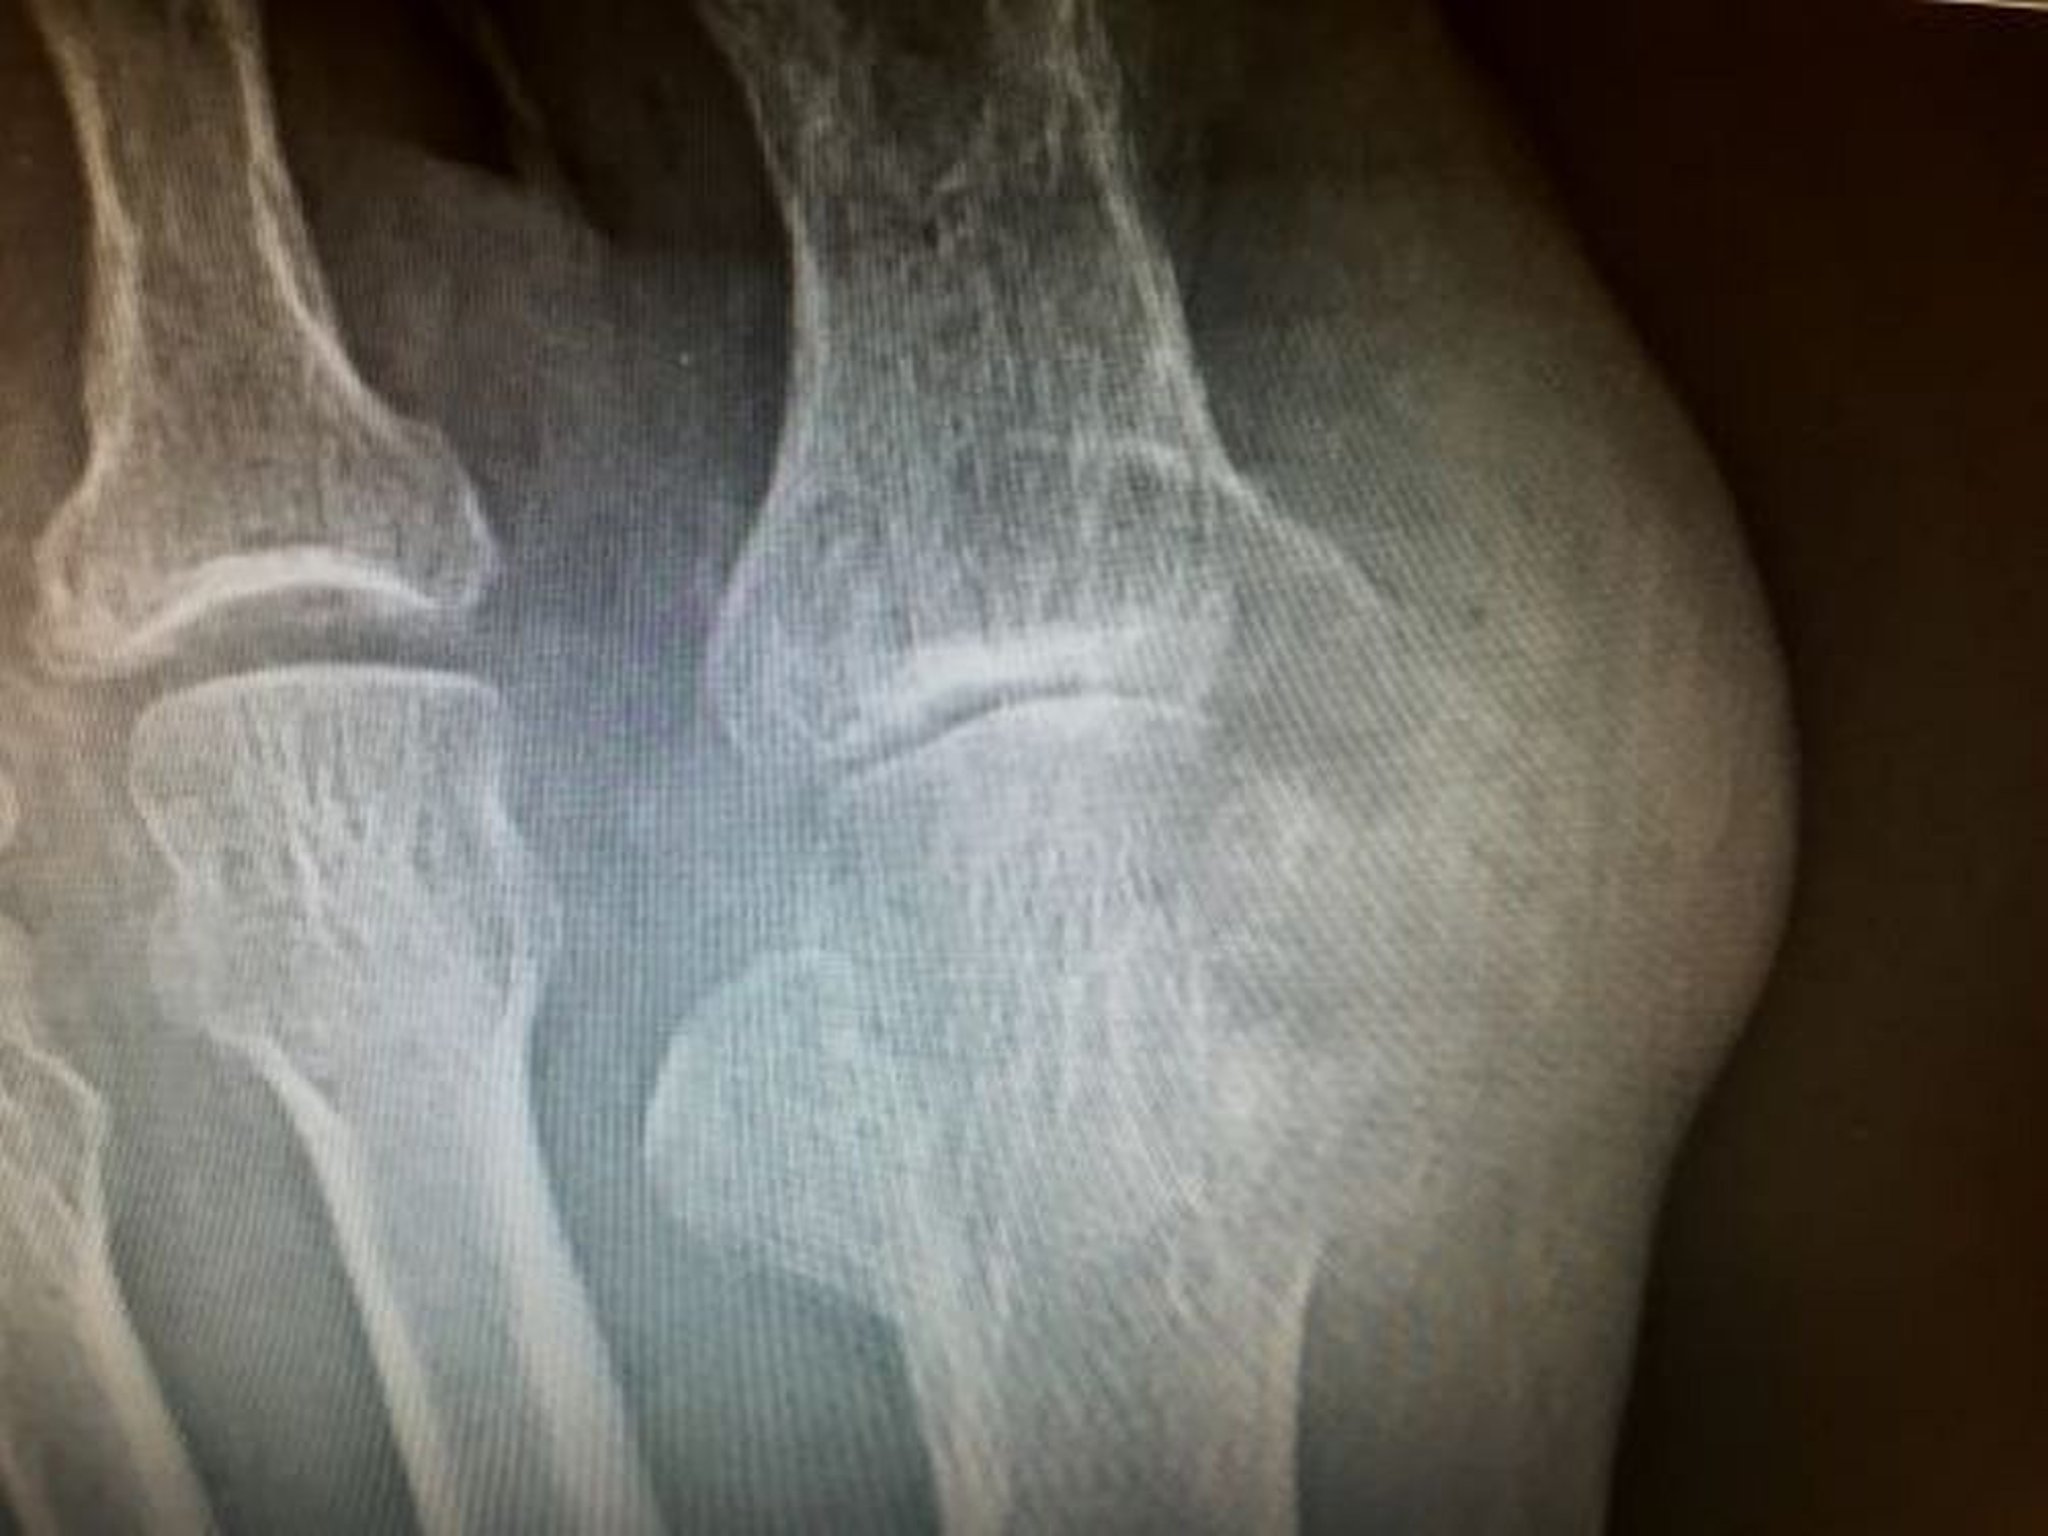

びらんを伴う痛風結節

この写真には,母趾の中足骨遠位部および基節骨を侵している痛風結節により生じた大きなびらんが写っている。

Image courtesy of N.Lawrence Edwards, MD.